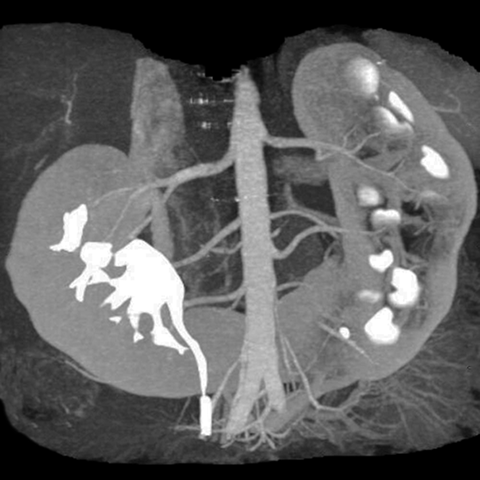

12 year old male presents with occasional abdominal discomfort [3 of 4]